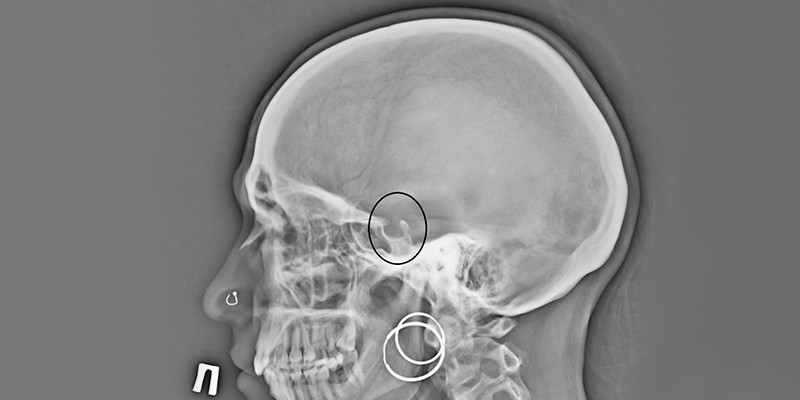

Рентген

В прошлые десятилетия основным методом диагностики опухоли гипофиза была рентгенография турецкого седла. Сейчас почти полностью ее вытеснили МРТ и КТ. Это связано с тем, что на рентгене плохо отображаются мягкие ткани, в отличие от томографии, где тело человека визуализируется в виде множества срезов. С помощью рентгенографии невозможно выявить микроаденому гипофиза. Сегодня рентгенография считается вспомогательным методом диагностики, при котором обнаруживаются характерные признаки и последствия аденомы:

- остеопороз (деструкцию ткани кости);

- двухконтурность дна турецкого седла.